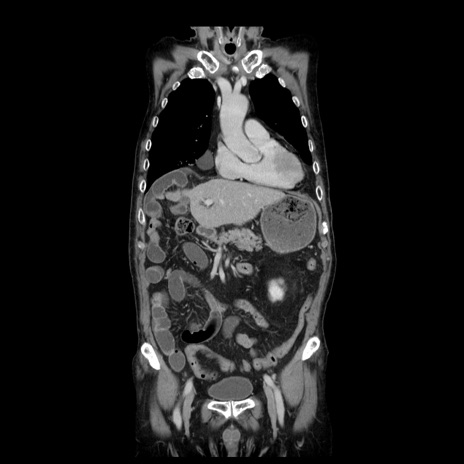

症例21(冠状断像)

【症例】70歳代男性

【主訴】腹痛

【現病歴】肝硬変・肝細胞癌にてかかりつけの方。約9時間前に食後より腹痛出現。症状が徐々に増悪し、嘔吐出現したため来院。

【既往歴】肝硬変、肝細胞癌(RFA、TACE後)

【身体所見】意識清明、表情苦悶様、BT 36℃、BP 129/78mmHg、P 88bpm、SpO2 97%(RA)、右上腹部から心窩部にかけて圧痛あり、反跳痛なし、筋性防御あり。

【データ】WBC 5800、CRP 0.16